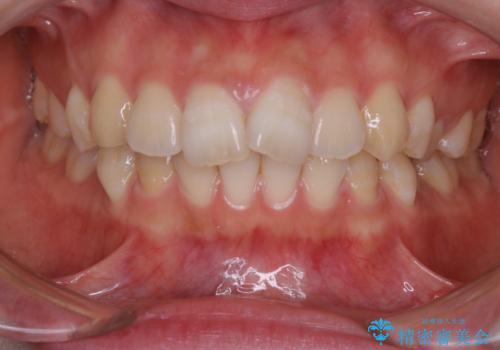

50代女性 マウスピース矯正 ディープバイト

ディープバイト症例に対するinvisalign矯正の一例です。

マウスピースそのものが咬合挙上の役割を併担してくれるため、ディープバイトはマウスピース矯正の好適用といえるかもしれません。

invisalign G5 がこれに相当するシステムです。

しかし、マウスピースの長期間使用により奥歯の咬み合わせが甘くなっており、今後保定の方法を工夫することでフォローしていく必要がありそうですね。

非常に真面目に装着していただき、追加アライナーなしでの動的治療終了となりました。